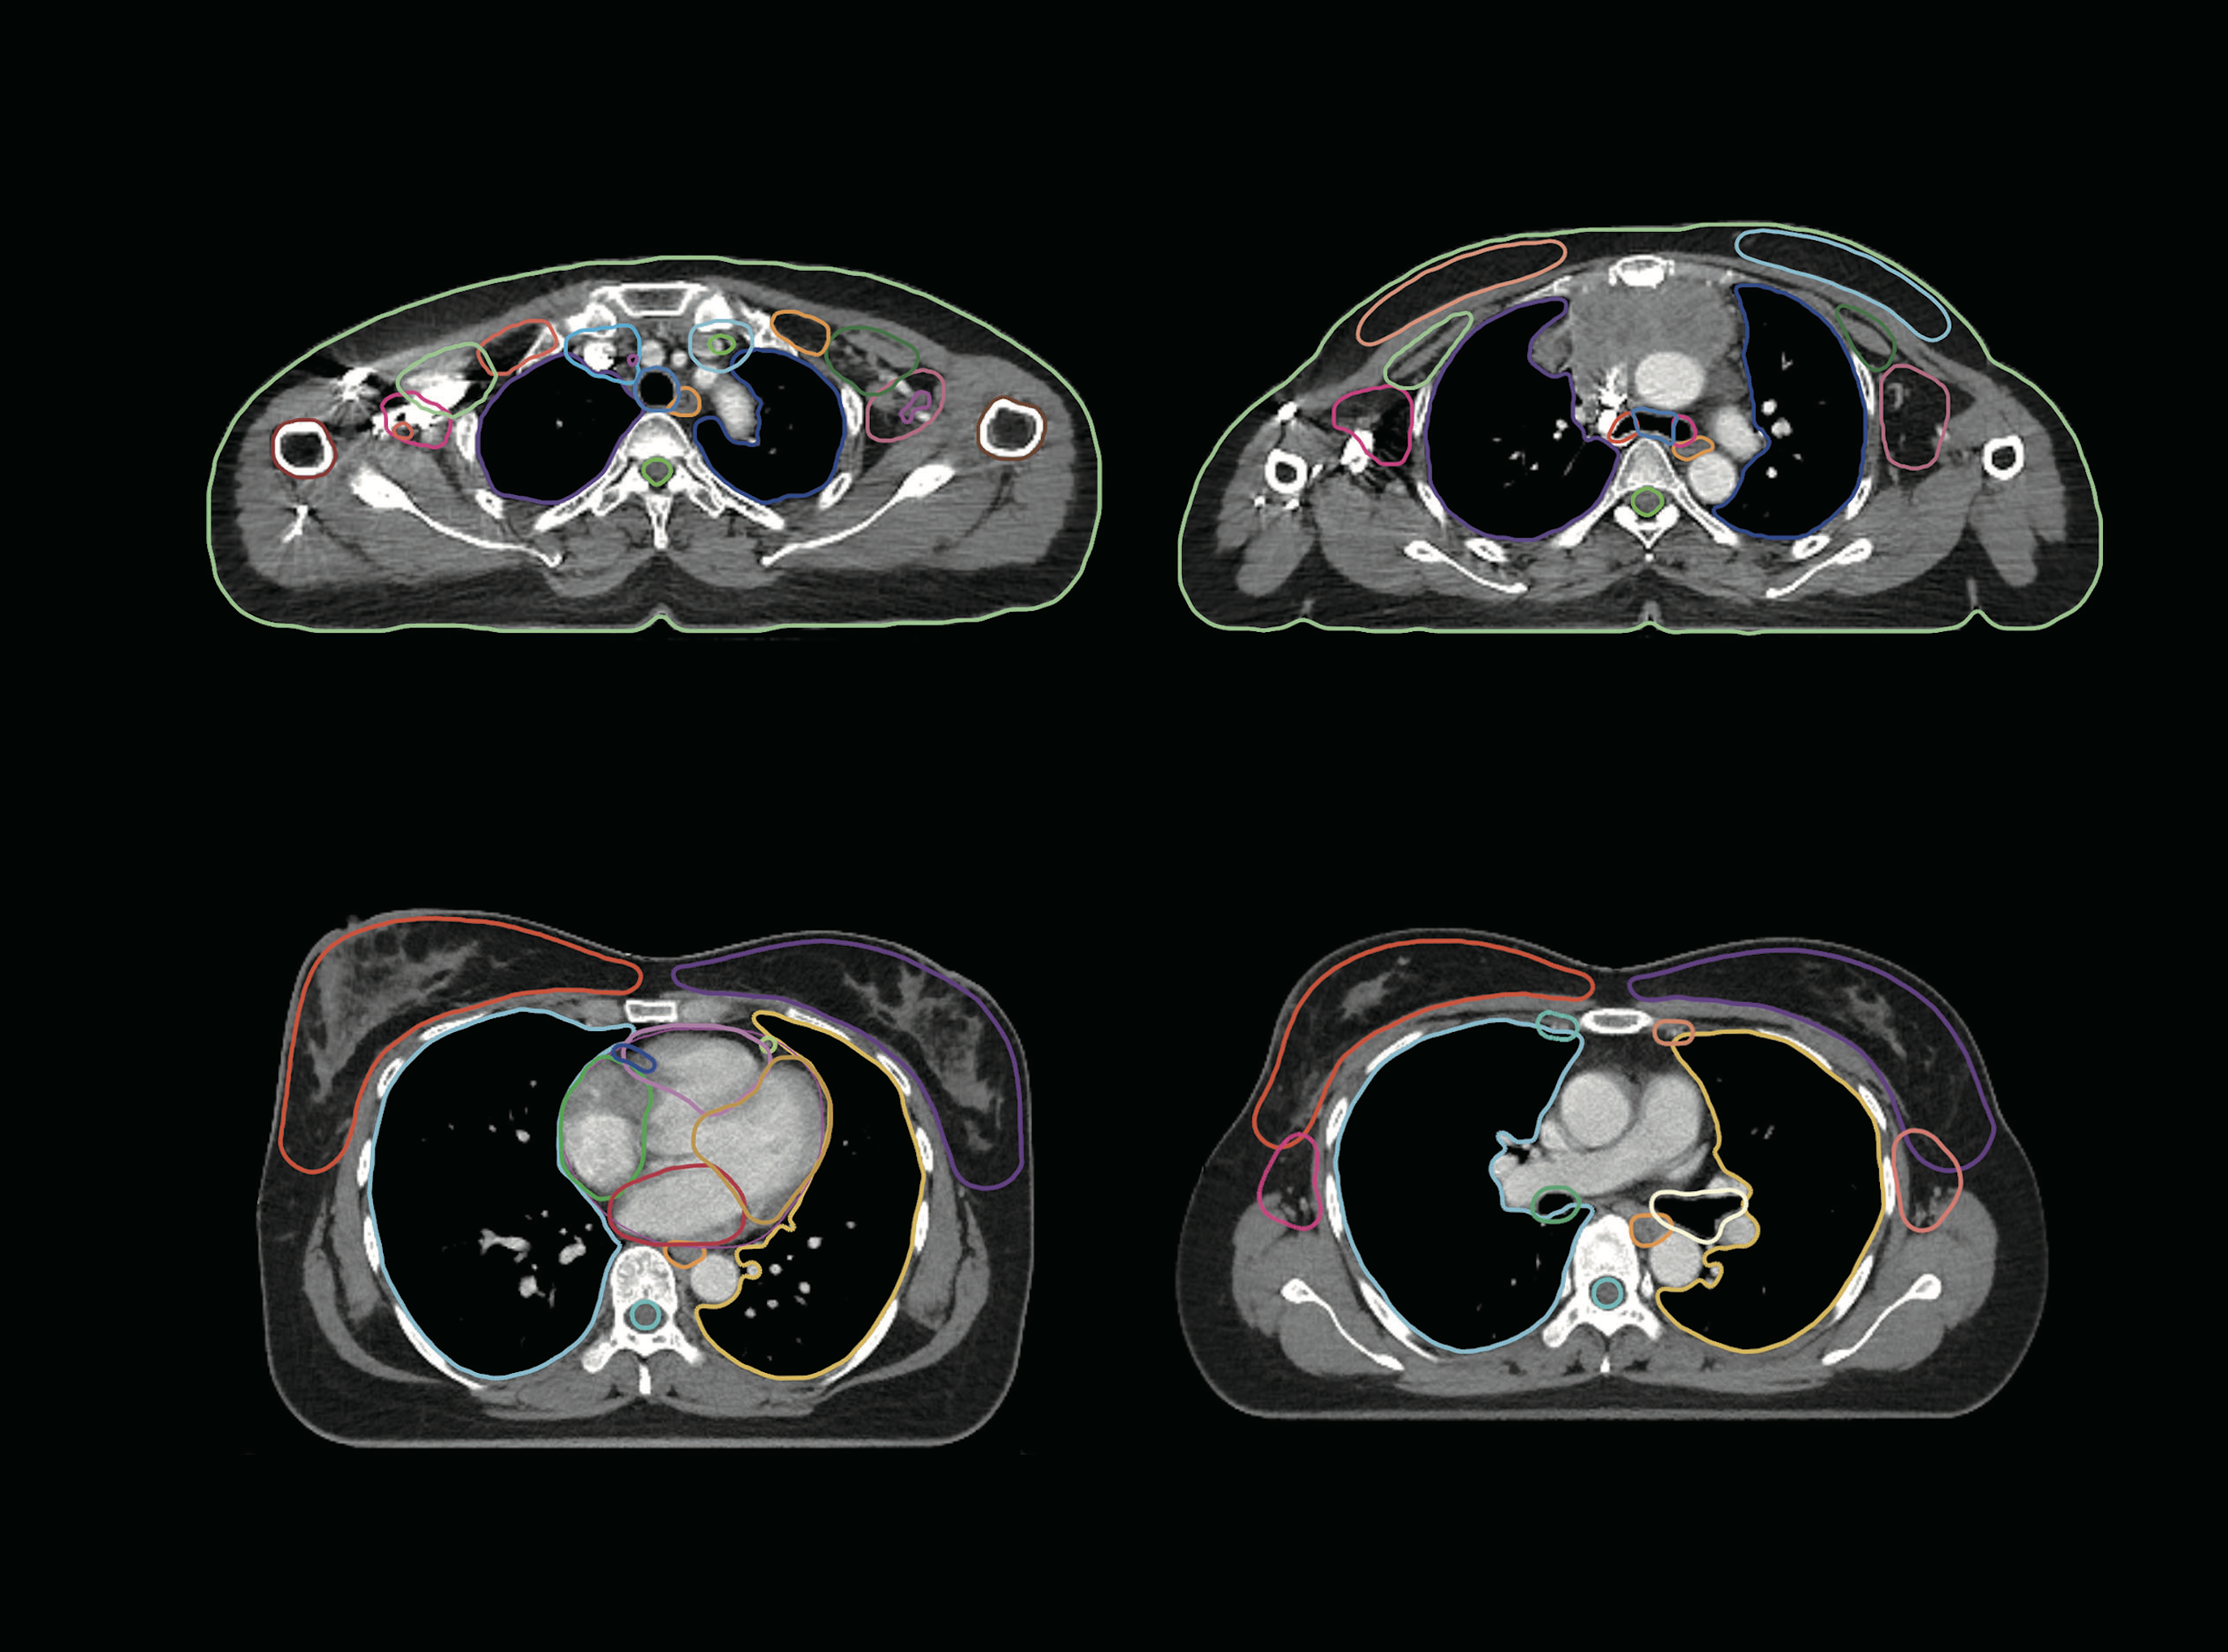

Utilizing AI technology, it automatically detects treatment areas and prepares organ contour samples. without any additional user input.

Key organs provided by OncoStudio are drawn within an average of 1 min/case.

It generates consistent contours akin to those subjected to expert-level accuracy through peer review.

A_Aorta

A_Coronary_R

A_LAD

A_Subclavian_L/R

Atrium_L/R

Body

Brachiocephalic_Trunk

Breast_L/R

Bronchus_L/R

Chestwall

Clavicle_L/R

Costal_Cartilages

ErectorSpinae_L/R

Heart

Humerus_L/R

LN_Breast_L1_L/R

LN_Breast_L2_L/R

LN_Breast_L3_L/R

LN_Breast_L4_L/R

LN_Breast_Sclav_L/R

LN_IMN_L/R

LungL/R

Lung_LLL

Lung_LUL

Lung_RLL

Lung_RML

Lung_RUL

Rib01_L/R

Rib02_L/R

Rib03_L/R

Rib04_L/R

Rib05_L/R

Rib06_L/R

Rib07_L/R

Rib08_L/R

Rib09_L/R

Rib10_L/R

Rib11_L/R

Rib12_L/R

Scapula_L/R

SpinalCord_PRV

Sternum

Trachea

V_Brachioceph_L/R

V_Pulmonary

V_Venacava_I

V_Venacava_S

VB_T01

VB_T02

VB_T03

VB_T04

VB_T05

Ventricle L/R